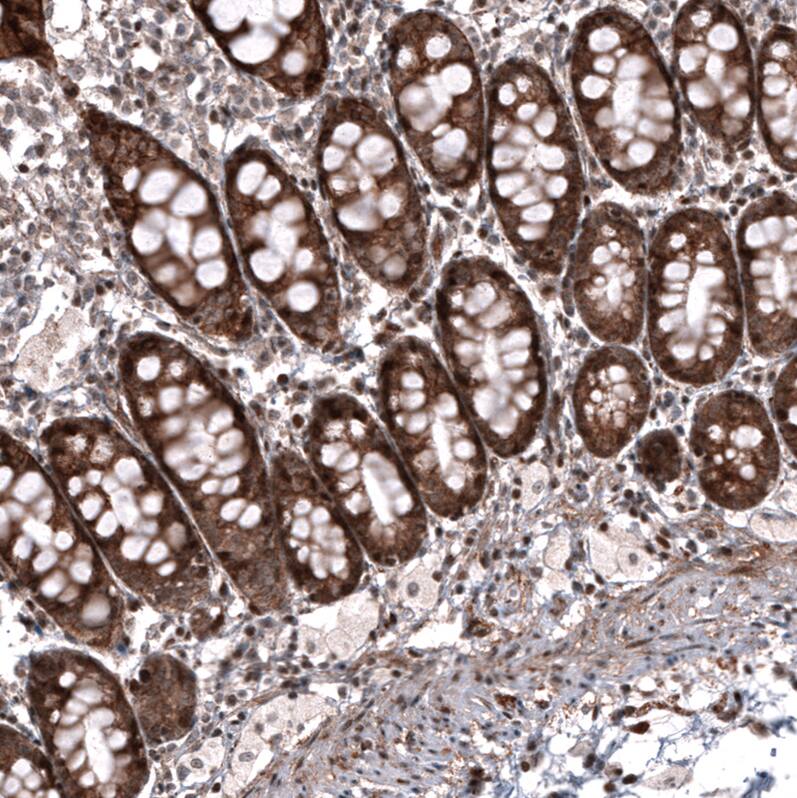

Staining of human colon shows strong positivity in glandular cells.